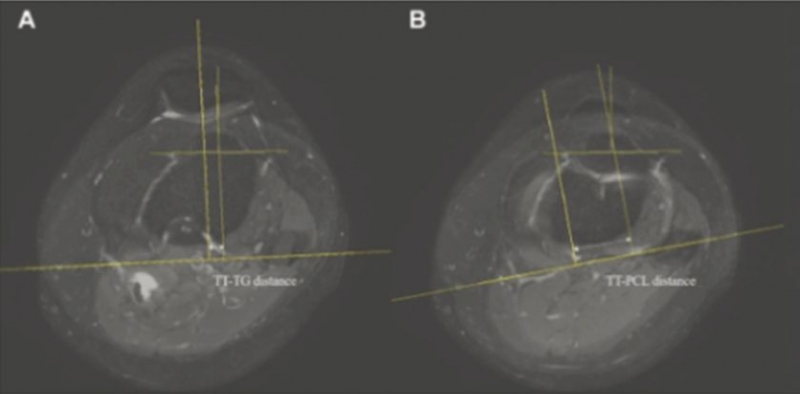

성인의 경우 경골결절과 활차구 사이(TT-TG) 및 경골결절과 후방십자인대 사이(TT-PCL) 거리로 불균형 여부를 판단하고, 슬개골을 제자리로 되돌리는 ‘원위부 재정렬 수술’을 시행한다.

이에 연구팀 분석결과 정상군에 속한 소아의 TT-TG 거리는 8.2mm, TT-PCL 거리는 19.5mm인 것으로 나타났다.

이는 불안정성군의 TT-TG 및 TT-PCL 거리인 16.1mm와 24.4mm와 비교해 유의하게 작은 수준이다.

또한 정상군에 속한 소아청소년의 TT-TG 및 TT-PCL 거리는 각각 15세, 11세까지 매년 증가하는 것을 확인할 수 있었다.

특히 연구팀은 분석을 통해 소아청소년의 TT-TG 거리 14.9mm, 또는 TT-PCL 거리 23.7mm를 슬개골 불안정성 위험이 높아지는 기준 값으로 제시했다.